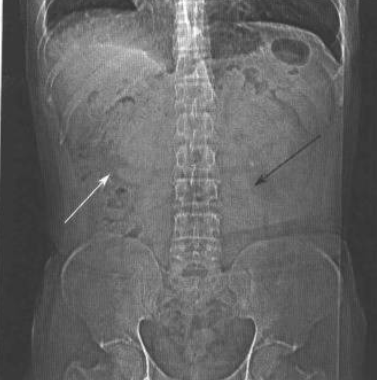

肾脏影像学检查中最简单易行的就是照泌尿系统平片。正常泌尿系统平片上,应可见两侧肾脏轮廓清楚,腰肌阴影对称,骨骼清晰可见,小肠内无积气,整个泌尿系统内无致密阴影,无软组织肿块阴影(图1)。

图片

图1 正常泌尿系统平片